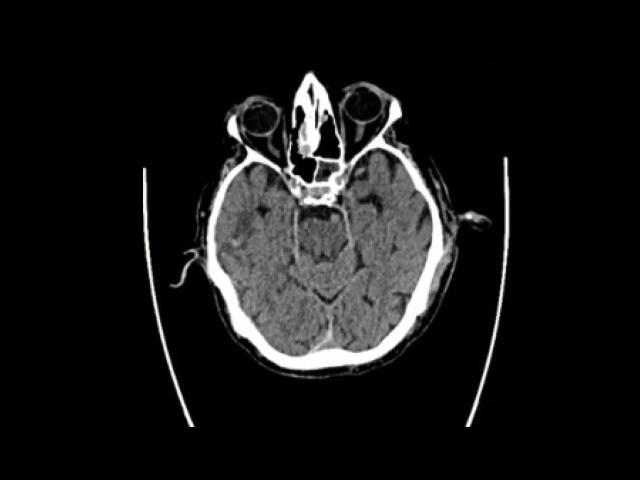

Sample Gallery